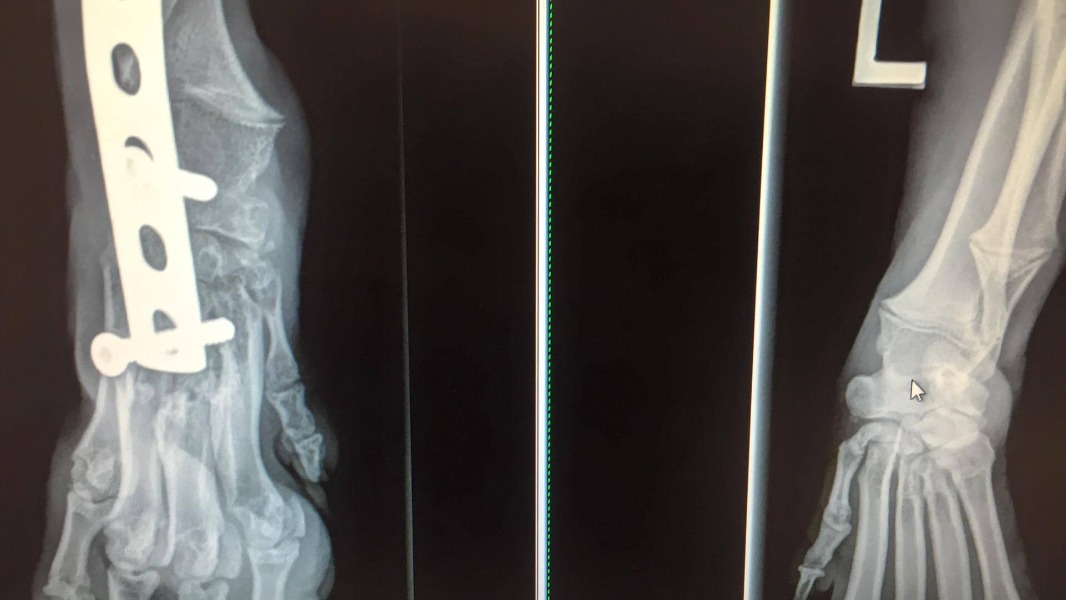

Source : @OzzieMiracleLe chien restera deux moins à la clinique où il subira plusieurs interventions chirurgicales pour l'aider à récupérer de ses multiples blessures. Lesmédecins installeront notamment une broche dans sa patte cassée.

Mais l'état de santé d'Ozzie ne s'est pas stabilisé, au contraire. Pendant sonséjour dans la clinique thaïlandaise, le chien a développé une gale sévère et plusieurs lésions nerveuses. La broche installée sur sa patte a par ailleurs provoquéune déformation du membre et une graveinfection des os.

L'avenir de sa patte est en revanche plus incertain. Plusieurs interventions chirurgicales ont été nécessaires pourextraire la broche mais l'infection de l'os est toujours sérieuse et les vétérinaires envisagent, dans le pire des scenarios, une amputation.Espérons que Ozzie pourra rejoindre sa famille en Australie sans en passer par là. Si vous souhaitez participer aux frais médicaux du chiot, c'est par ici.Le couple a indiqué quel'excédent servira à fournir du matériel médical aux vétérinaires de l'île de Koh Sang en Thaïlande, là d'où vient Ozzie."Il aurait déjà dû être mort au moins dix fois. Il va s'en sortir haut à la main, très heureux et en parfaite santé", a confié le couple avec optimisme.